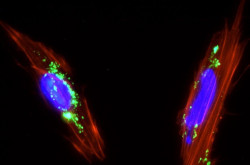

Los científicos dan un paso importante hacia el uso de trasplantes de células de retina para tratar la ceguera

Células de la retina derivadas de un ojo humano de cadáver sobrevivieron cuando se trasplantaron a ojos de modelos de primates, un avance importante en el desarrollo de la terapia celular para tratar la ceguera, según un estudio publicado en la revista `Stem Cell Reports`.